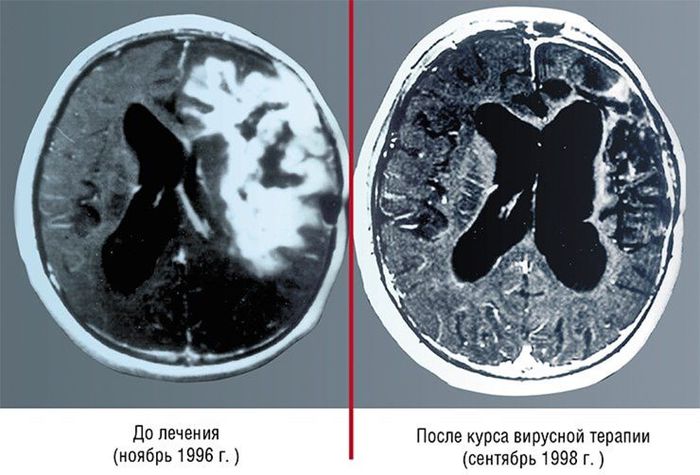

Эти томограммы служат свидетельством одного из самых поразительных случаев излечения рака с помощью вирусной терапии. Больной – пятнадцатилетний подросток с глиобластомой, наиболее опасной и быстро развивающейся опухолью головного мозга. Лечение проводилось вирусом болезни Ньюкастла – опухоль занимала значительный объем головного мозга и никакое иное терапевтическое вмешательство было невозможным. По устному сообщению одного из авторов этой публикации, пациент на 2013 г. был жив и успешно работал. По: (Csataryand, Bakacs, 1999). Цит. по: (Нетесов, Чумаков, 2013)